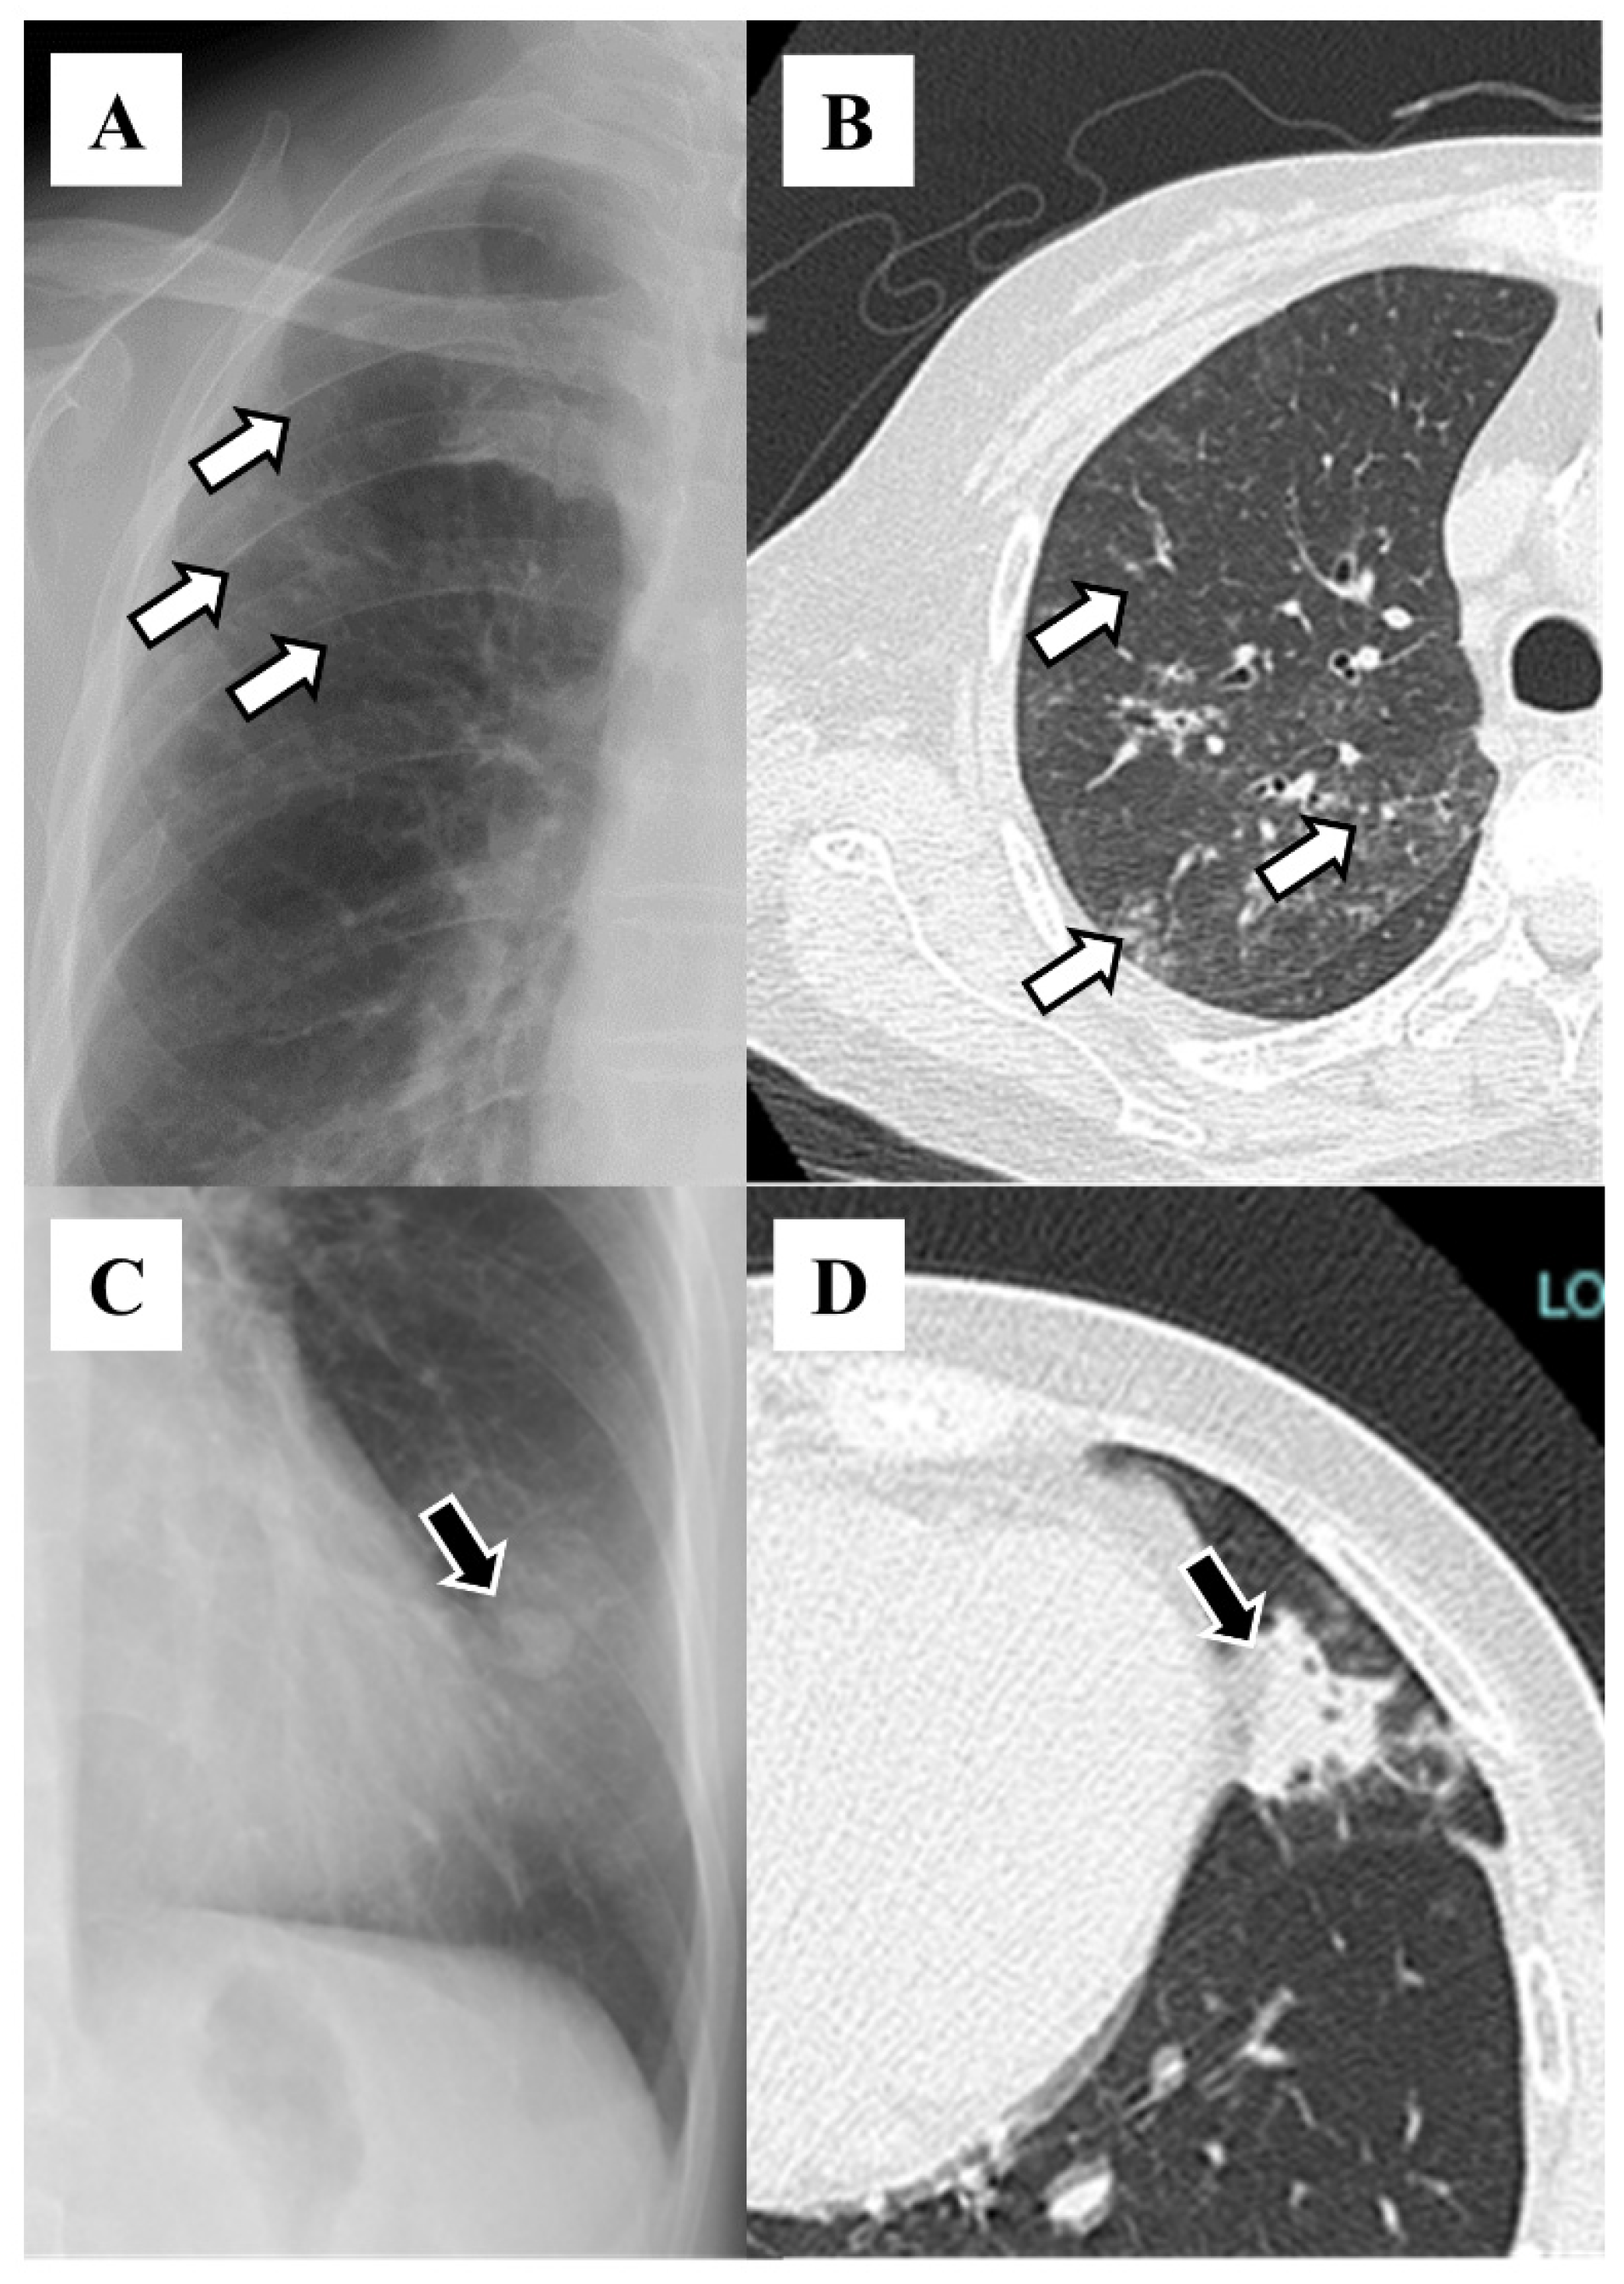

| Tram-track appearance | 46 (35.4) |

| Ring sign | 32 (24.6) |